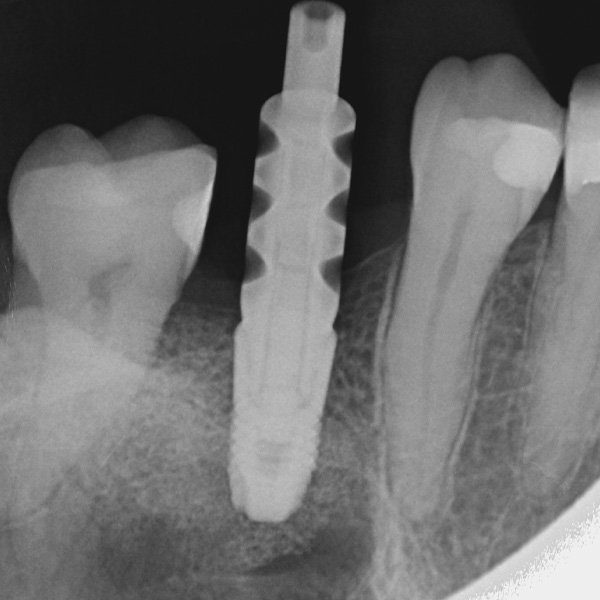

Ricostruzione coronale implantare, in ceramica ibrida VITA ENAMIC multiColor

Restauri supportati da impianti sono soggetti a carichi particolarmente elevati. Dopo l‘estrazione e l‘impianto al paziente manca l‘apparato di fibre elastiche del letto dentale naturale. Per questo motivo le forze di masticazione non vengono assorbite, ma trasmesse direttamente sul restauro, l‘impianto, l‘osso e la dentatura antagonista. La ceramica ibrida VITA ENAMIC ha una struttura a reticolo duale in ceramica (86 % in peso) e polimero (14 in peso). Ne risulta un‘elasticità simile alla dentina e la capacità do assorbire le forze di masticazione. Il blocchetto policromo VITA ENAMIC multiColor in geometria EMC-16, grazie alla sua elevata dimensione verticale, consente di realizzare corone-abutment monoblocco, monolitiche anche nel caso di osso atrofizzato. L‘odontoiatra Professor Dr. Alexander Hassel mostra in questo contributo come riabilita una paziente con questa forma di restauro.